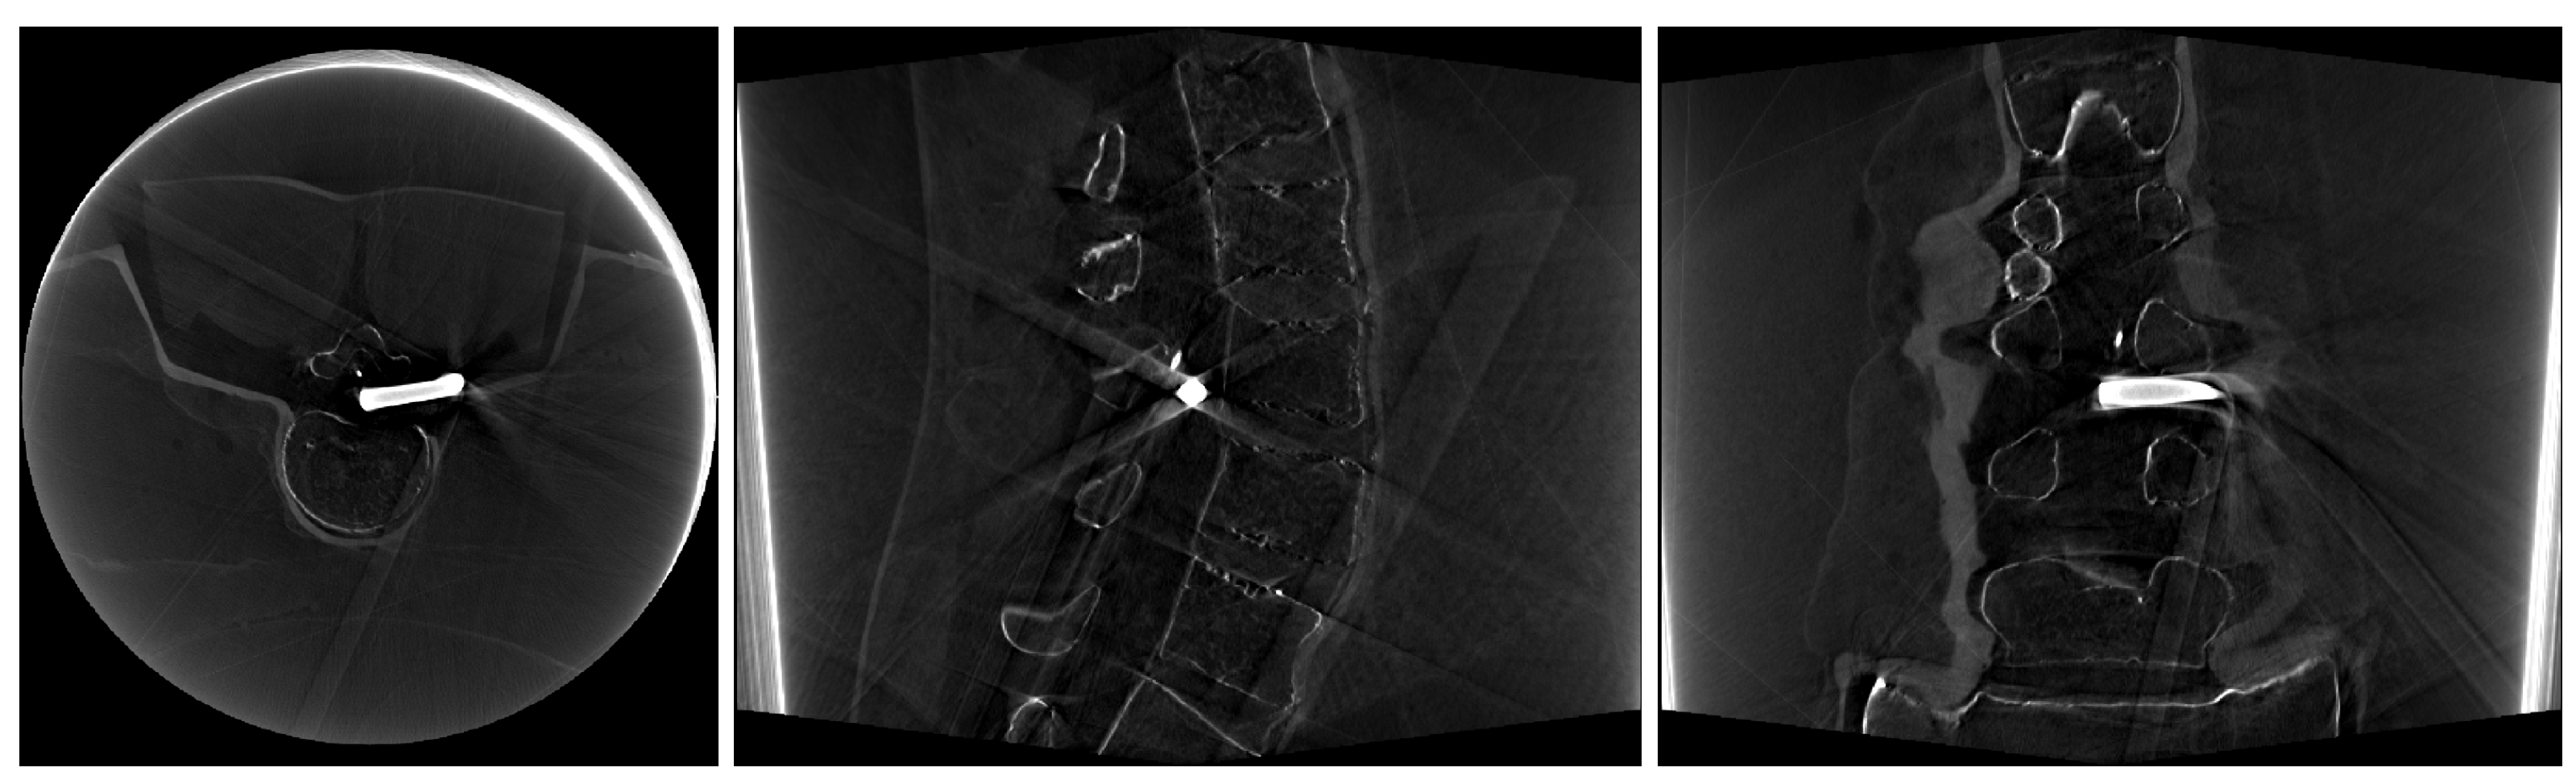

2. Materials and Methods

3. Results